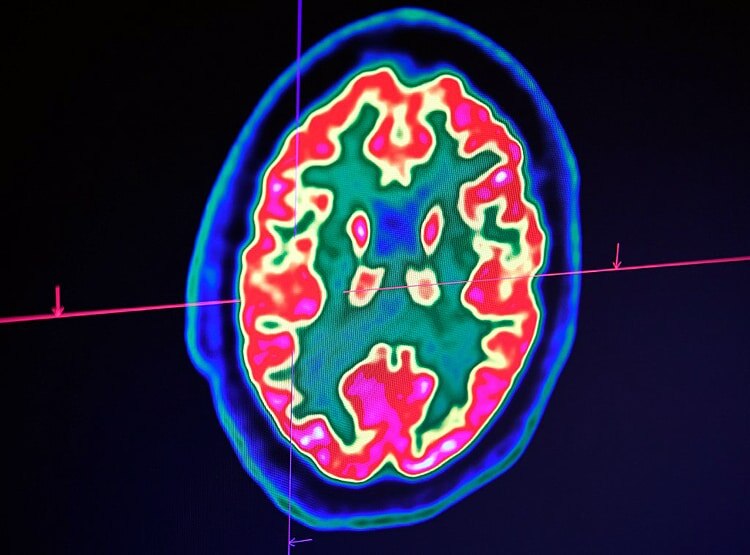

कोरोना वायरस शरीर में सिर्फ फेफड़ों पर ही असर नहीं करता. बल्कि आपके दिमाग पर भी बुरा असर डालता है. लंदन के वैज्ञानिकों ने बताया है कि कोरोना वायरस की वजह से दिमाग काम करना कम कर देता है. इसका नर्वस सिस्टम पर असर पड़ता है. दिमाग की नसों में सूजन आ जाती है. संक्रमित इंसान फिजूल बातें सोचता है. फालतू की बातें करने लगता है. (फोटोः AFP)

यूनिवर्सिटी कॉलेज लंदन के वैज्ञानिकों ने कोरोना से जूझ रहे 43 मरीजों के दिमाग की जांच की. उनको निगरानी में रखा तो पता चला कि कोरोना वायरस की वजह से मरीजों के दिमाग की नसें सूज जा रही हैं. मनोविकृति हो रही है. वे बेवजह बातें करने लगते हैं. (फोटोः AFP)